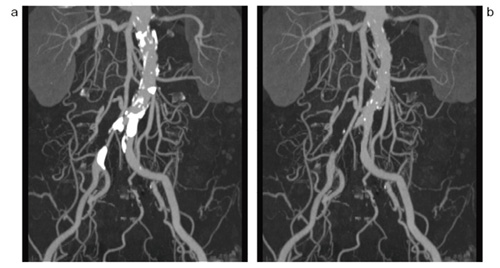

さらに,単なる骨の分離だけでなく,図1のように石灰化の分離もできるため,従来は困難であった石灰化を伴う血管の内腔評価も可能となる。

図1 Dual Energyイメージングによる石灰化と血管の分離

本症例は右総腸骨動脈が閉塞した症例である。煩雑な作業を行うことなく,短時間でaのように骨と血管の分離を行うことができる。さらに,bのように石灰化も除去することができるため,通常の撮影では困難であった石灰化を伴う血管の内腔評価が可能となる。

(画像ご提供:奈良県立医科大学様)